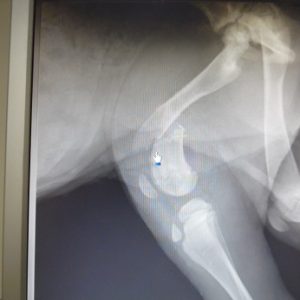

H μικρούλα, μια κουταβίνα 3,5 μηνων. Εμφανίσθηκε στους Γαργαλιάνους με έντονη ψώρα και αδυναμία. Μαζί με όλα, χτυπηθηκε από αυτοκίνητο και έχει σπασμένο μηριαίο.

Τις 3 πρωτες μέρες ήταν σε κατάσταση σοκ. Είχε άρνηση για τροφή και δεν σηκωνόταν. Πιστευαμε οτι δεν θα τα καταφέρει. Της χορηγούσαμε αντιβιωτικά και ορό στο σπίτι όπου φιλοξενούνταν.Όμως η μικρούλα είναι μαχητής και συνήλθε. Μεταφέρθηκε για φιλοξενία στο Καταφύγιο Αδέσποτων Ζώων (ΚΑΖ) στο Μαρκοπουλο και θα χειρουργηθεί τη Δευτέρα.Το κόστος ανέρχεται σε 300 ευρω.

Η Πραλίνα΄μια μικρή γκριφονίτσα που βρέθηκε δεμένη κάτω από ένα φορτηγό, είναι περίπου 8 μηνών και έχει σπασμένη κεφαλή στο μηρό.

Χρειάζεται να χειρουργηθεί και το κόστος θα είναι στα 300ευρω.

Η Πραλίνα χειρουργήθηκε εχθές στις 10 Ιουλίου 2014 και ήρθε σήμερα στο καταφύγιο. Η εγχείρηση είχε επιτυχία (πώς θα μπορούσε να είναι κι αλλιώς αφού την έκανε ο μάγος Νίκος Καραμήτσος) αφαιρέθηκε η κεφαλή του μηριαίου και το κοριτσάκι μας επέστρεψε για να αρχίσει τα τρεχαλητά σε λίγες μέρες. Το κλουβί από εχθές μέχρι σήμερα που την πήραμε της έπεσε λίγο στενό και για να περάσει την ώρα της άρχισε το ξήλωμα. Πάνε τρία ράμματα, εξ ου και το λαμπαντέρ στις φωτο.